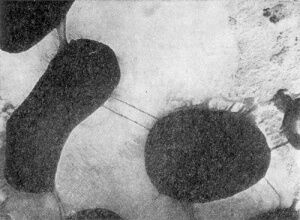

Все микобактерии неподвижны, окрашиваются по Граму положительно. На ранней стадии развития (впервые сутки) микобактерий имеют палочковидное строение клеток, и в этот момент они морфологически похожи на проактиномицетов, находящихся во второй стадии развития. Палочковидные клетки микобактерий, в отличие от бактериальных, имеют неправильные очертания: контуры их искривлены, в разных местах они неодинаковой толщины, часто колбовидно раздутые, клетки более или менее изогнуты, одиночные или соединены в пары или короткие цепочки (рис 2.1).

Рис.2.1 Клетки Mycobacterium

Цепочки никогда не бывают правильно очерченными и прямыми, строго расположенными в одну линию, как это наблюдается в культурах бактерий; обычно они угловато искривленные. На рисунке 2.2 показан общий вид односуточных культур разных видов микобактерий, наиболее типичных по своему строению и расположению клеток. Величина клеток микобактерий меняется в зависимости от вида культуры и состава среды. В молодом возрасте чаще всего клетки имеют длину 2,5 - 7,0 мкм [5].

Другим характерным морфологическим признаком микобактерий является ветвление. Ветки образуются на боковой поверхности палочковидных клеток. Степень ветвления у разных микобактерий неодинакова: у одних клетки при благоприятных условиях образуют многочисленные ветки, по 2 - 5 на каждой клетке, у других обычно по 1 - 2 ветки. У многих видов ветвящиеся клетки встречаются вообще редко, а на некоторых средах вообще не обнаруживаются. Наконец, имеется много культур, у которых ветвление обнаруживается только при особых условиях культивирования. Например, у синих (Mycobacterium cyaneum) и черных (Mycobacterium nigrum) микобактерий ветвления на обычных средах (МПА, сусло-агар) не наблюдается, клетки имеют бактериальное строение; при посеве их на ломтики картофеля или в жидкие среды обнаруживается большое количество типичных ветвящихся клеток. Следовательно, ветвление у микобактерий зависит в значительной степени от питательной среды [5].